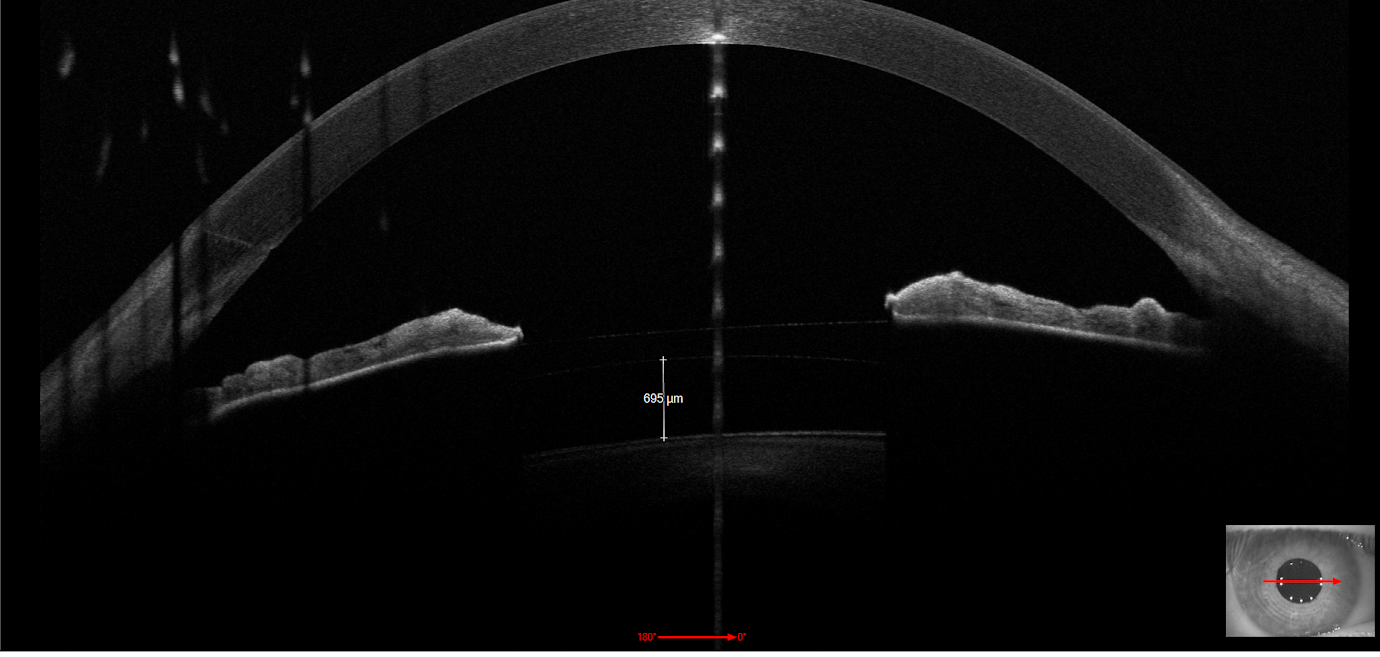

6 ICL per correzione miopia in paziente con cheratocono

Paziente di 35 anni miopi di 3.50 diottrie in entrambi gli occhi. Gli accertamenti pre operatori hanno evidenziato la presenza di un iniziale cheratocono che controindicava la chirurgia di correzione della miopia con laser ad eccimeri. Dopo aver valutato la stabilità nel tempo del cheratocono a distanza di due anni in considerazione della volontà del paziente di correggere la miopia è stato consigliato l'impianto di lenti intraoculari ICL. Il risultato a un mese dall'impianto è di 10/10 naturali il decorso post operatorio è stato regolare il posizionamento delle lenti è ottimale (vedi OCT segmento anteriore).

Le lenti ICL possono essere utilizzate in vari casi per correggere i difetti refrattivi (miopia, astigmatismo, ipermetropia) in particolare quando non è possibile utilizzare il laser ad eccimeri per controindicazioni.  (patologie corneali come i cheratocono, miopie elevate...).